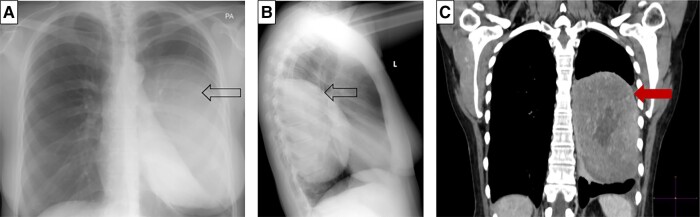

Investigations during a spontaneous hypoglycemic episode, confirmed with a serum glucose level of 18 mg/dL (1.0 mmol/L), showed an appropriately suppressed C-peptide of 0.03 nmol/L (normal reference range [NR], <0.2; 0.1 μg/L [NR, <0.6 μg/L]); insulin 1.39 pmol/L (NR, <20.8; 0.2 mIU/L [NR, <3 mIU/L]); and β-hydroxybutyrate of 0.2 mmol/L (NR, 0-0.5 mmol/L). The cortisol response was appropriately elevated for the degree of hypoglycemia. Biochemistry was not in keeping with hyperinsulinemia and further investigations were directed at confirming NICTH. The patient’s results were consistent with the diagnosis of NICTH, whereby there was a reduced insulin-like growth factor 1 (IGF-I) level of 5.2 nmol/L (NR, 5.6-22.9 nmol/L), with an elevated insulin-like growth factor 2 (IGF-II) of 220 nmol/L, and a 4-fold increase in the IGF-II:IGF-I ratio of 42.3 (NR < 3) [1‐3]. The diagnosis was further supported by a low IGF binding protein 3 (IGFBP3) of 3.3 mg/L (NR 3.4-6.9; 3.3 μg/mL [NR, 3.4-6.9 μg/mL]) and suppressed growth hormone (GH) of less than 0.1 μg/L (NR, 0.13-9.88 μg/L). Localization images included a chest radiograph that showed an opacification involving the left lower and mid zones (Fig. 1A and 1B). This was further delineated on computed tomography of the chest, showing a well-defined, left pleural–based mass measuring 9.7 × 11.8 × 11.8 cm (Fig. 1C). A primary pleural tumor producing IGF-II was considered the most likely cause of the hypoglycemia.

Figure 1.

Localization images. A and B, Chest radiograph showing a left pleural–based mass (indicated by arrow): A, posteroanterior; B, lateral. C, Computed tomography of the chest showed a well-delineated, left pleural–based mass measuring 9.7 × 11.8 × 11.8 cm (red arrow).